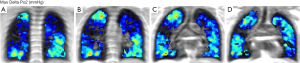

Scintigraphy

A different imaging modality, which can be used in the evaluation of severe lung emphysema is scintigraphy (Figure 3). With scintigraphy it is possible to visualize ventilation and perfusion of the lungs. With this method upper-lobe predominance and heterogeneity of emphysematous lung changes can be visualized and combined with functional data such as perfusion. The technique is especially helpful in the evaluation for the detection of severely emphysema affected areas in the lung in heterogeneous emphysema, but struggles in subjects with a homogeneous distribution of emphysema (36). In scintigraphy the lung is divided in three distinct zones (i.e., upper, middle and lower zonr). Information on tracer uptake, corresponding to ventilation and perfusion, are provided for these three distinct lung zones.

Some authors, despite the high agreement between lung perfusion evaluated on HRCT and on scintigraphy, criticize scintigraphy for the lack of additional information to HRCT making scintigraphy superfluous in the assessment of lung emphysema (37,38).